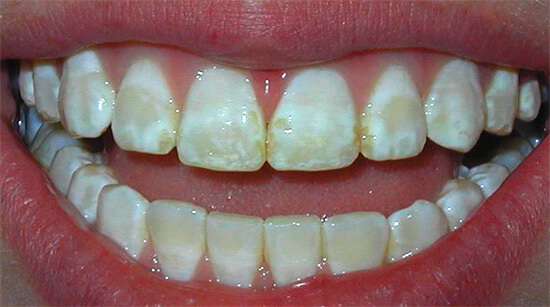

В норме зубная эмаль блестящая, гладкая. При флюорозе эмаль на пораженных участках тускнеет и белеет, становится словно мел. В дальнейшем эти участки могут накапливать пигмент и окрашиваться в желтый, коричневый цвет.

Пятнистая форма

Эта форма проявляется отчетливыми сплошными меловидными пятнами без полосатого рисунка на зубной эмали. Пятен обычно много и они разбросаны по всей поверхности зуба. Пятнышки могут сливаться в крупное пятно. Такие очажки поражения нередко приобретает коричневатый оттенок. При этом эмаль в этой области гладкая, блестящая. Пятнистая форма проявляется на всех зубах, но отчетливо выражена именно на резцах.